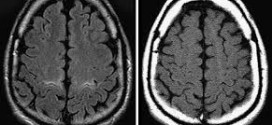

La Esclerosis Lateral Amiotrófica (ELA) con Demencia Frontotemporal, es el ejemplo más claro de enfermedad degenerativa del sistema motor, a lo largo de la evolución la familia puede ir observando cambios, a menudos sutiles, pero en ocasiones francos, de modificación del carácter o incluso deterioro intelectual. Frecuentemente el paciente disminuye su fluidez verbal, utiliza menos palabras, le cuesta ser preciso …

La Degeneración Espinocerebelosa es una enfermedad poco común que se transmite a través de las familias (hereditaria) y afecta los músculos y el corazón. Resumiendo: La Degeneración Espinocerebelosa es una enfermedad hereditaria que causa daño progresivo al sistema nervioso dando como resultado síntomas que varían desde perturbaciones de la marcha y problemas del lenguaje a la enfermedad cardíaca. La Degeneración …